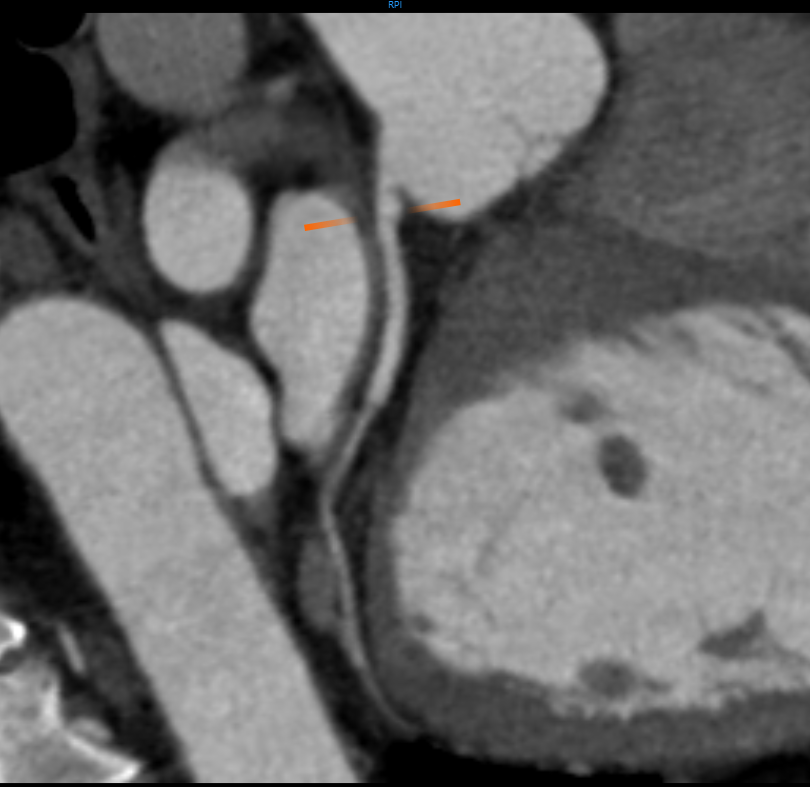

Aneurysms

An aneurysm is an abnormal bulge or weakened area in the wall of a blood vessel. Using detailed CT imaging, doctors can accurately visualize the size, shape, and precise location of an aneurysm — whether in the brain, aorta, or other vessels. This enables early diagnosis before a potential rupture, which is critical for preventing life-threatening complications. CT scan machines also help evaluate rupture risk by tracking growth over time and guide decisions regarding treatment, such as surgery, endovascular stent placement, or continued monitoring.